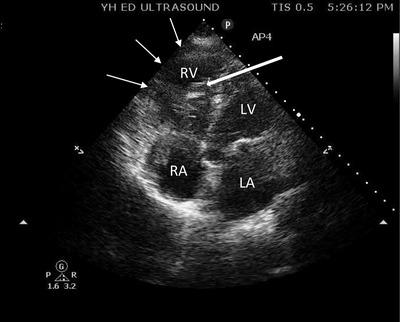

Elderly woman with shortness of breath.